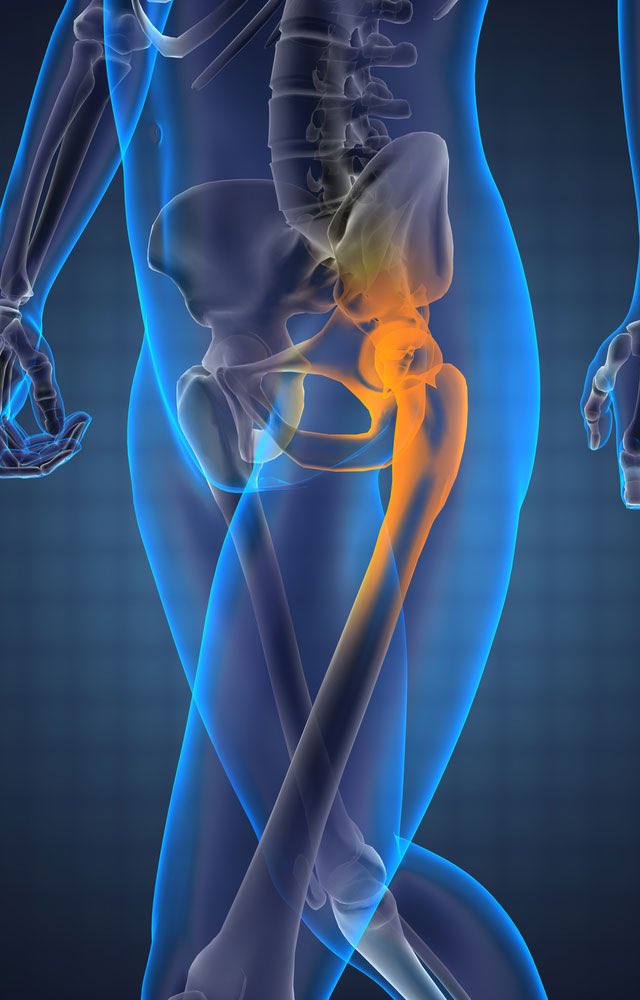

١-ألم في الجزء الخارجي من الورك وأعلى الفخذ جانبًا.

٢-ألم عند الاستلقاء على الجانب المصاب.

٣-ألم عند الحركات المتكررة مثل: القيام من الكرسي، واستخدام السلالم أو الدرج، والخروج من السيارة والجري.